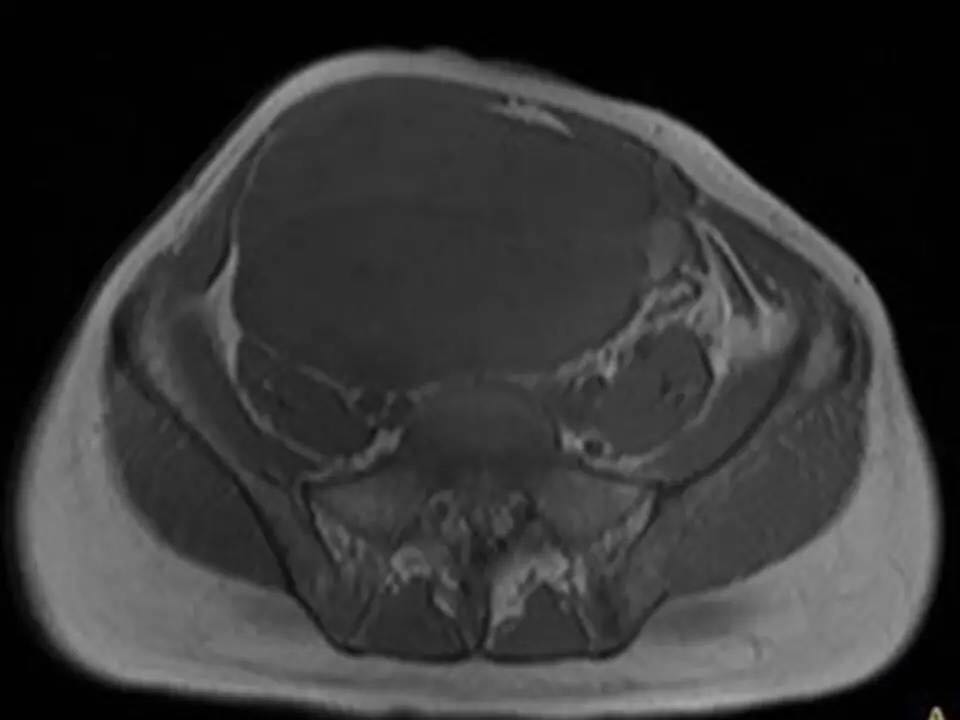

MRI表现,腹盆腔见不均质肿块,与肌肉相比为等低密度,强化不明显。T1WI信号均匀,T2WI高低混杂信号,增强后渐进性强化,病变各序列可见斑片状低信号区。 诊断,腹腔侵袭性纤维瘤病。

AF的影像学表现具有一定特征性。影像上表现为边界欠清的软组织肿块,钙化、出血少见,即便在较大的肿瘤中也看不到中央性坏死。病灶CT密度欠均匀,与邻近骨骼肌相近,强化不明显。T1WI信号基本均匀,明显或中度强化,典型强化方式呈渐进性。所有序列中都可以看到一定的低信号区,在病理上相对应的为病变内胶原纤维丰富的区域,此区域强化较轻。 侵袭性纤维瘤病虽然少见,但是平常工作中需要考虑到侵袭性纤维瘤病的诊断,尤其是中年女性腹腔的肿块。MRI为最佳的检查方法,可以显示一定的影像学特征。